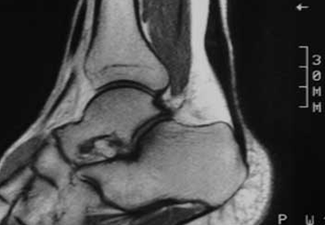

Resonancia magnética nuclear donde se observa el engrosamiento del tendón de aquiles.